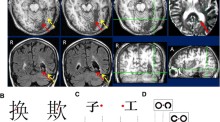

Left hemiparalexia of Chinese characters: neglect dyslexia or disruption of pathway of visual word form processing? Wenchao YiTing WuXuchu Weng Original Article 09 January 2013 Pages: 283 - 292